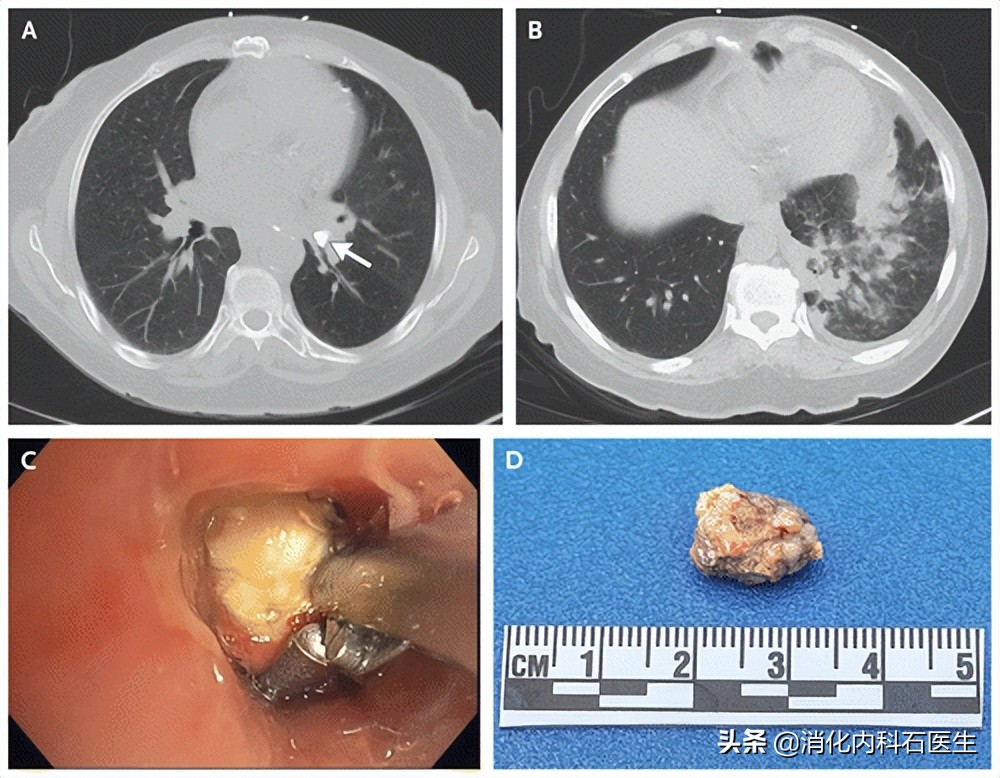

胸部CT显示:右肺叶不张,下叶实变影。

一周后复查胸部CT:炎症减轻了,但是肺部确实还有一个肿物一样的东西。

第一次气管镜结果:

右侧中叶气管见一不规则状的新生物阻塞支气管,主支气管管腔内见大量的脓性分泌物!

于是,第二次气管镜检查:

医生一看到支气管的肿物后就去活检,但是肿物太软了,每次一碰就会冒出大量的脓液,没办法医生只能反复地灌洗(冲洗)。

大约折腾了一个小时后,医生累得大汗淋漓。

正要放弃时突然一个不规则的黄色异物出现在医生的视野中!

医生顿时打起来十二分的精神,继续反复地冲洗,必须搞清楚这是个什么东西。

或许就是这个东西惹的祸!

反复地冲洗下,只见一个不规则的黄色异物逐渐露出真面目,医生取出来后定睛一看:

怎么是块石头?!

继续来到右下叶内侧支气管基底段,也看见同样的略小的黄色异物,医生小心翼翼地反复多次予以取出。

折磨老张20余年的罪魁祸首原来只是几块小结石!

之后老张麻醉清醒,出现剧烈的咳嗽,之后咳出来了多个小颗粒状的小结石。

1周后,再次复查胸部CT团块状肿物影基本消失。